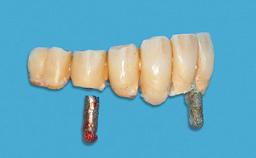

Mandibular Overdenture Supported by a CAD/CAM-milled Bar with Long Distal Extensions on Two Conventionally Loaded Implants

An 87-year-old man was referred to our Division of Gerodontology and Removable Prosthodontics at the University Clinics of Dental Medicine, Geneva, Switzerland for dental implant therapy. He was retired and led a very active social life, keeping himself busy in the company of his many grandchildren and with frequent travels to Italy. The patient’s past medical and drug histories revealed that he suffered from angina, asthma, and arthritis of the knee. He was allergic to penicillin. His regular prescription medications included anti-anginal and antiasthmatic drugs, along with occasional non-steroidal anti- inflammatory drugs for joint pain. Otherwise, he was a healthy patient who occasionally consumed alcohol on social occasions and did not smoke. A detailed dental history revealed that he had lost his teeth to chronic adult periodontal disease and had had an edentulous maxilla for over 20 years.